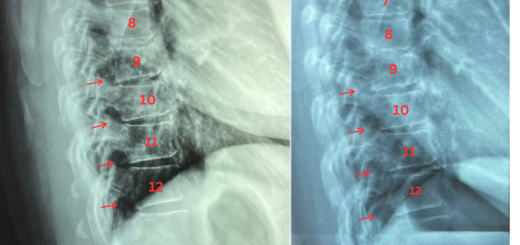

Disc degeneration reversal